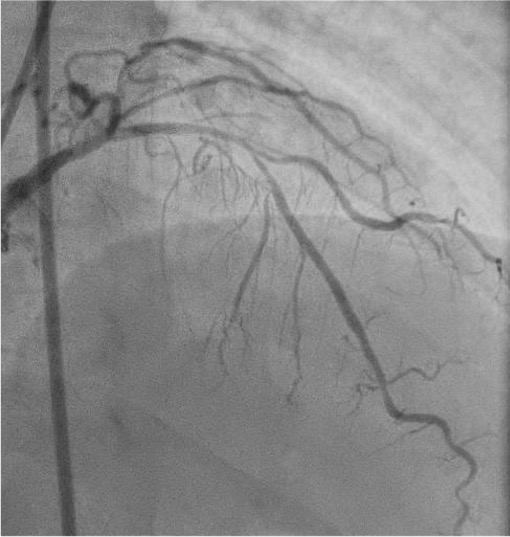

Coronary angiography via the radial approach showed a severe proximal LCx stenosis and a long, severe mid-LAD stenosis, while the RCA had no significant disease. IVUS of the LAD demonstrated diffuse calcification and an eccentric calcified plaque protruding from the septal side near the diagonal branch bifurcation. The guidewire was biased toward the diagonal branch, causing tenting of the relatively healthy wall at the most critical segment.

PCI was first performed for the LCx, using orbital atherectomy followed by cutting balloon predilatation and drug-coated balloon therapy with good angiographic result. One month later, PCI was attempted for the LAD lesion using a 8F system via right femoral approach. Intravascular ultrasound (IVUS) revealed a diffusely eccentric calcified plaque located on the septal side. While wire bias in the proximal segment was toward the calcified plaque, the distal segment showed tenting of the wire toward a plaque-free site on the diagonal branch side. At this point, we considered that debulking of the distal segment would be a high risk of vessel injury. We hypothesized that performing proximal segment debulking that had a favorable wire bias might shift the overall wire bias toward the septal side. Then Only proximal OAS was performed using pull-back ablation.Follow-up IVUS showed disappearance of distal tenting and favorable wire bias toward the calcified plaque. As a result, OAS was safely performed in the distal segment as well. Additional debulking of the residual calcified plaque was conducted with a 2.0 mm Rotablator. IVUS confirmed effective debulking without vessel injury in the area of concern. The entire lesion was then dilated with a CB; however, a dissection with hematoma occurred, and a drug-eluting stent (DES) was implanted. Final IVUS demonstrated acceptable stent expansion, and final angiography showed no residual stenosis or flow limitation.